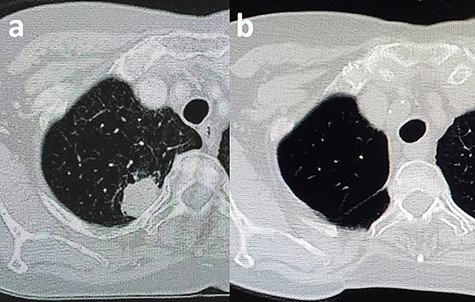

A 67-year-old woman was referred to our hospital because of cough and sputum production. A chest computed tomography (CT) scan showed a 26 × 20 mm mass in the posterior segment of the right upper lobe adjacent to the third rib’s neck and head (Fig. 1a). No mediastinal lymphadenopathy was observed. Pathological examination with transbronchial tumor biopsy revealed lung adenocarcinoma. Positron emission tomography/CT scans and brain magnetic resonance imaging indicated no evidence of distant metastasis.

CT scan of the chest. (a) Shown is a tumor located adjacent to the rib’s neck and head. (b) This postoperation image shows the complete resection of the rib’s neck and head.

There were no adverse events after the operation, and the patient was discharged on postoperative Day 7. The final pathological report revealed a 23 × 20 mm mass infiltrating the resected chest wall’s soft tissue close to the resected rib neck, and the surgical margin was negative. There was no evidence of recurrence on the 12-month follow-up CT scan (Fig. 1b).